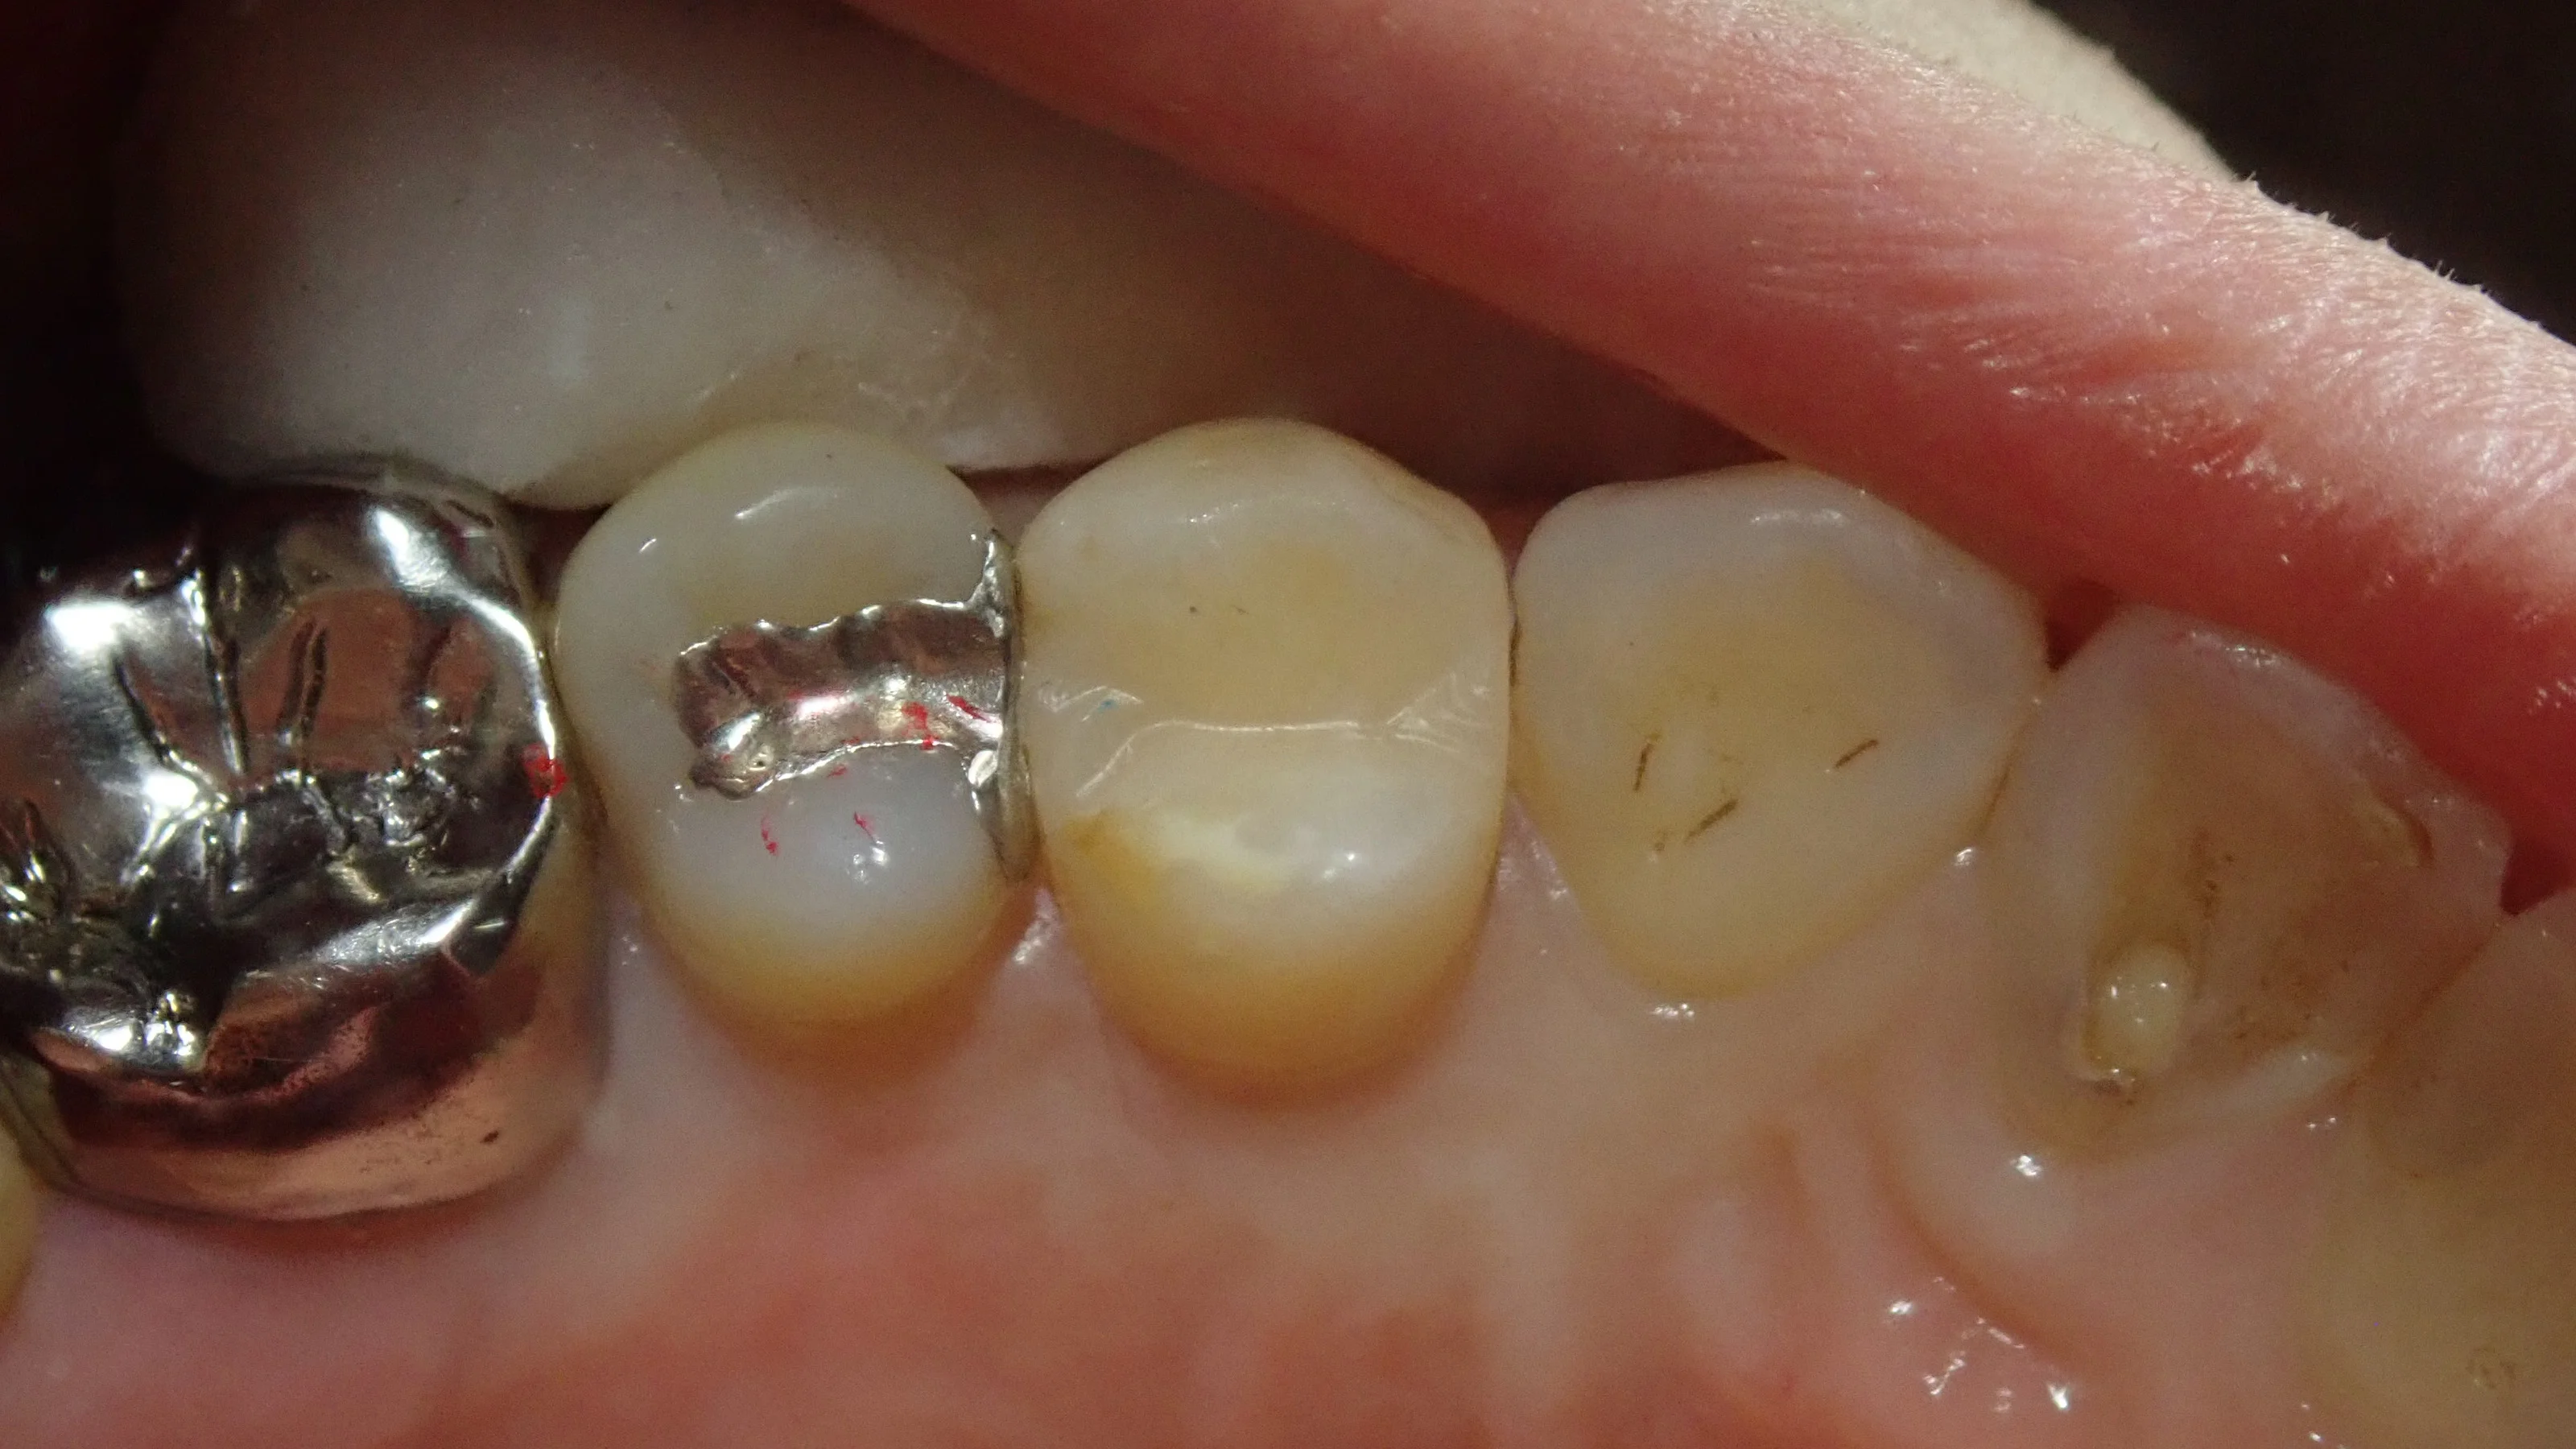

そして金属を除去したての写真がこちら。

セメントが残存していますが、両隣の歯に面している部分が黒くなっているのが分かるかと思います。

ちょっとわかりづらいので、セメントを除去しきった写真も載せます。

こうなると結構黒いのが分かると思います。

手前の歯との間については黒い部分だけではなく、あからさまに歯が柔らかくなっているのが確認できます。(写真のちょっと白いところ)